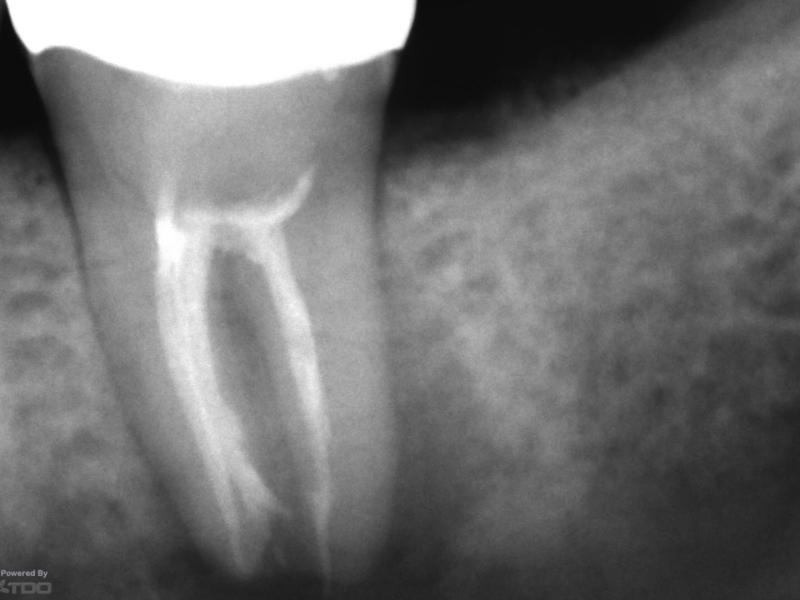

Pre-Op